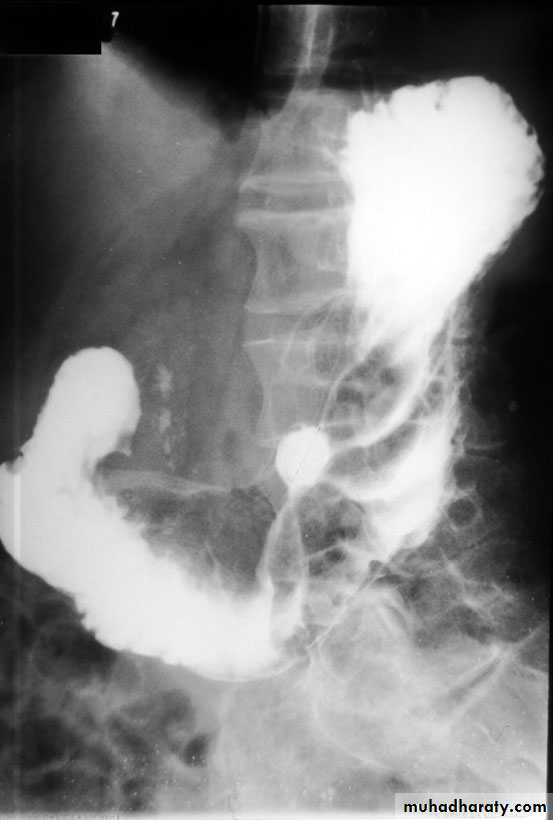

2- Barium studies DU appears as a well-demarcated crater, most often seen in the bulb. Benign GU also appears as a discrete crater with radiating mucosal folds originating from the ulcer margin. Ulcers >3 cm in size or associ. with a mass are more often malignant.